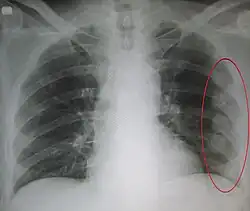

| An X ray showing multiple old fractured ribs of the person's left side as marked by the oval | |

Plain X-rays often pick up displaced fractures but often miss undisplaced fractures.[13] CT scanning is generally able to pick up both types of fractures.[13]

Right sided pneumothorax and rib fractures -